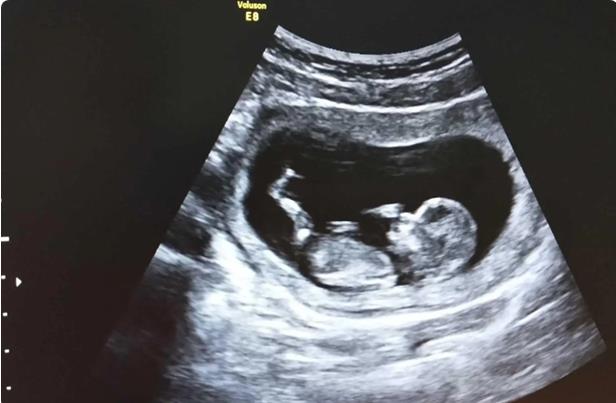

如果患者有子宫内膜损伤、子宫腺肌病、子宫内膜炎、子宫内膜息肉或其他子宫内膜病变,胚胎无法着床,成功率也会受到影响。即使胚胎成功着床,不良的宫内环境也会造成流产,对母体和胎儿的安全造成极大的威胁。一般如果子宫异常,无法治愈,就不能做手术。

胚胎需要好的宫腔环境

宫腔环境对于成功妊娠有十分重要的影响,子宫内膜息肉、子宫内膜炎、粘膜下子宫肌瘤或是宫腔形态异常(如子宫纵隔)等都是常见的会影响妊娠的不利因素,它们会恣无忌惮的破环子宫这片富饶的土地,影响胚胎着床。